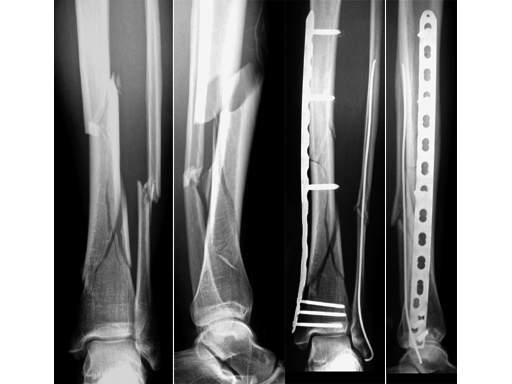

32-year-old woman, closed fracture type 42-C3 with minimal soft-tissue injury, after skiing accident.